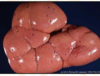

Acute renal infarct

Acute renal infarct after 2-3d

infarct of an entire kidney

large renal infarct